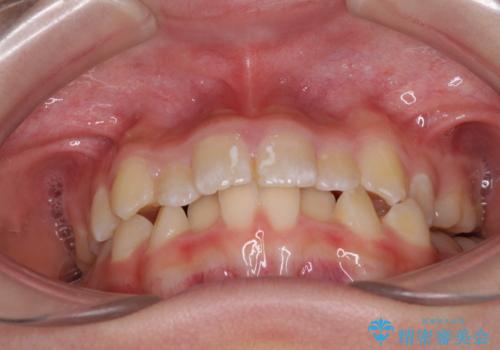

- 小児矯正の頃から診察を行っている患者様です。

上顎骨の幅が下顎骨よりも小さいので、拡大装置により骨幅を広げて上下関係を改善し、その後インビザラインにて歯並びを整えることとしました。